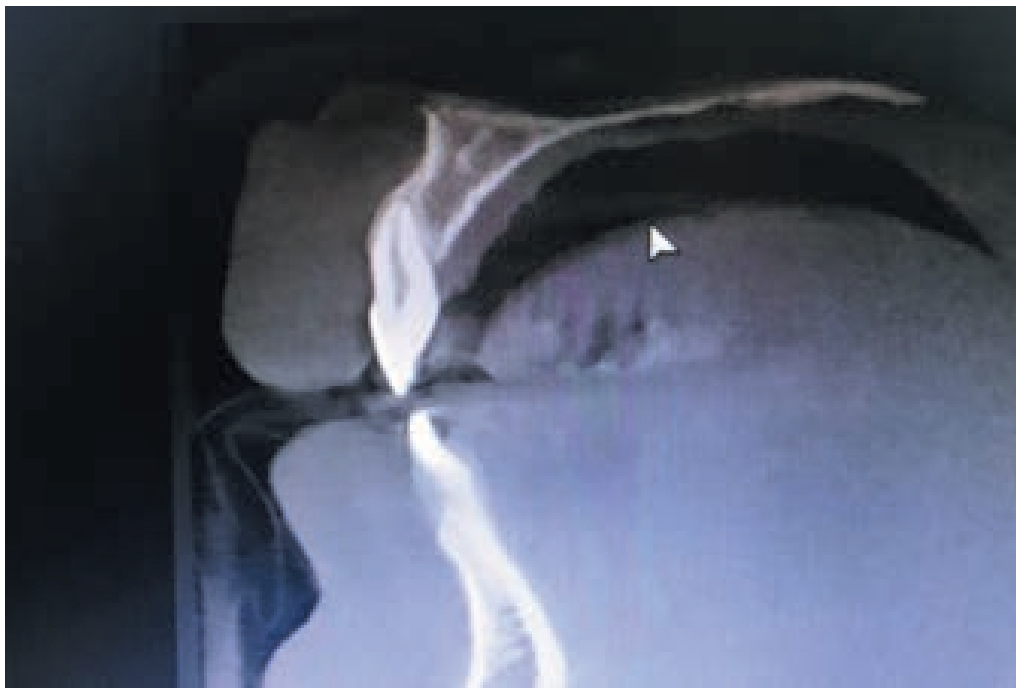

Рецессия десны возникает при сочетании нескольких факторов. Протокол комплексного ортодонтическо-хирургического лечения данной патологии индивидуален для каждого пациента и зависит от его возраста, этиологии, глубины и степени поражения, места локализации процесса. При отказе от лечения патологический процесс усугублялся в постоянном прикусе. Ортопантомограмма как метод диагностики для оценки толщины кортикальной кости у резцов малоинформативна при данной патологии и следует отдавать предпочтение диагностической конусно-лучевой компьютерной томографии (рис. 8).

Рис. 8. КЛКТ пациента перед ортодонтическим лечением